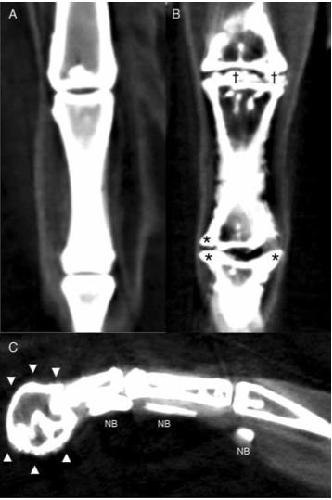

Figure 3. Reconstructed dorsal plane CT image of a normal MTP and IP joint (A), reconstructed dorsal plane CT image of a severely affected MTPjoint and IP joint (B) with periarticular new bone formation (as- terisks *) and new bone formation within the joint space (daggers â ), and reconstructed sagittal plane CT image of a severely affected digit (C) with a misshaped distal phalanx surrounded by a rim of new bone (arrowheads â²) and linear mineralization plantar to the digit within the extensor tendons (NB).